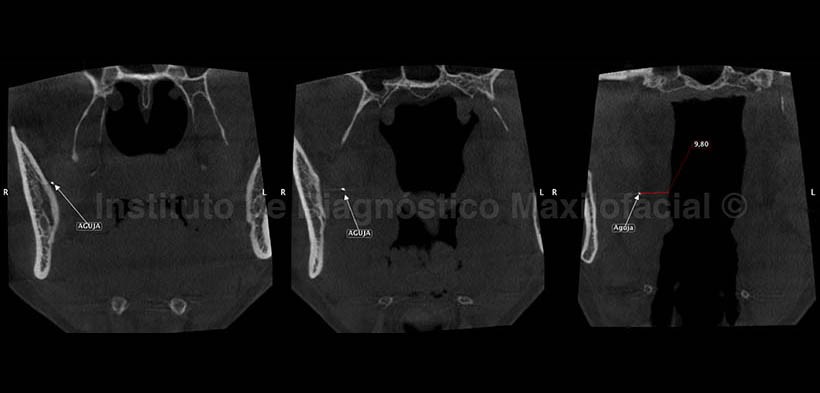

A la evaluación con tomografía volumétrica en los cortes axiales (Fig. 2), coronales (Fig. 3) y sagitales (Fig. 4) se aprecia la ubicación del cuerpo extraño en el espacio pterigomandibular del lado derecho. En la figura 2 se aprecia el extremo del objeto que se encuentra mas superior en proximidad con la cortical interna de la rama ascendente y el extremo inferior del objeto se encuentra cerca de la vía aérea orofaringea, nótese el compromiso de la furcación de la pieza 2.6 en la imagen axial de la izquierda. En la figura 3 se observa la distancia del objeto con relación a la vía aérea orofaringea, la cual es de 9.80 mm. En la figura 4 se observa la disposición anteroposterior de la aguja, nótese la calcificación pupar de la pieza 1.6 y la aparente lesion apical correspondiente a una tabicación intrasinusal, además del engrosamiento de la mucosa antral.